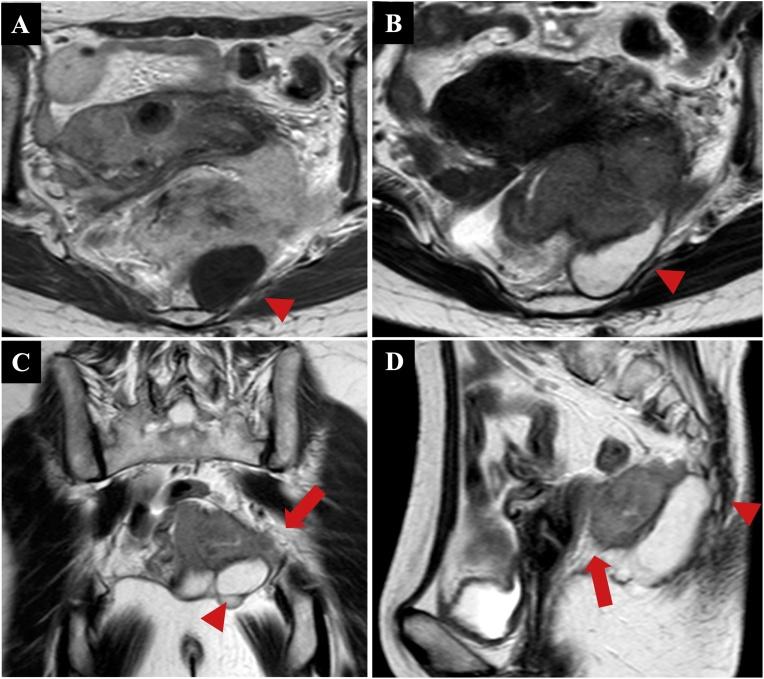

A 59-year-old woman complained of tenesmus and discomfort in the buttocks. Computed tomography revealed a 50-mm well-defined cystic mass in the presacrum and a 70-mm solid mass extending from the cyst into the rectum, vagina, and left sciatic spine. On T1-weighted magnetic resonance images, the cyst was unilocular and the mass was marginated with low intensity. On T2-weighted images, the mass had high intensity. A malignant presacral developmental cyst was diagnosed, without obvious metastasis. Using abdominal and parasacral approaches, Hartmann's operation was performed with multiorgan resection, including the sacrum, coccyx, left sciatic spine, internal obturator muscle, rectum, and uterine appendage. Histopathology of the excised specimen revealed a squamous cell carcinoma originating from the presacral epidermoid cyst.

Reports of malignant transformation of epidermoid cysts in the presacral space, as in the present case, are extremely rare. Because of their unusual location and slow growth, epidermoid cysts tend to remain asymptomatic. Because the patient had a malignant tumor with suspected invasion of adjacent organs, combination surgery was selected.

Although further research is required, presacral epidermoid cysts are extremely rare and may be malignant. Thorough preoperative image evaluation is crucial for complete resection.